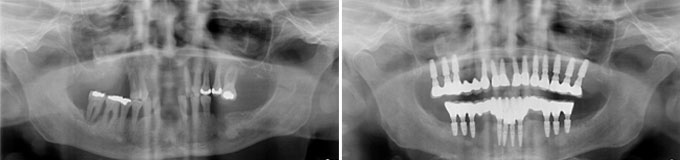

Il me manque de nombreuses dents, les autres sont perdues, je veux l’idéal.

Solution : on peut remplacer toutes vos racines manquantes ou perdues par autant de racines artificielles et vous redonner des dents fixes partout.

Toutes dents sont hélas perdues. Toutes les dents absentes sont remplacées par des couronnes sur implants.